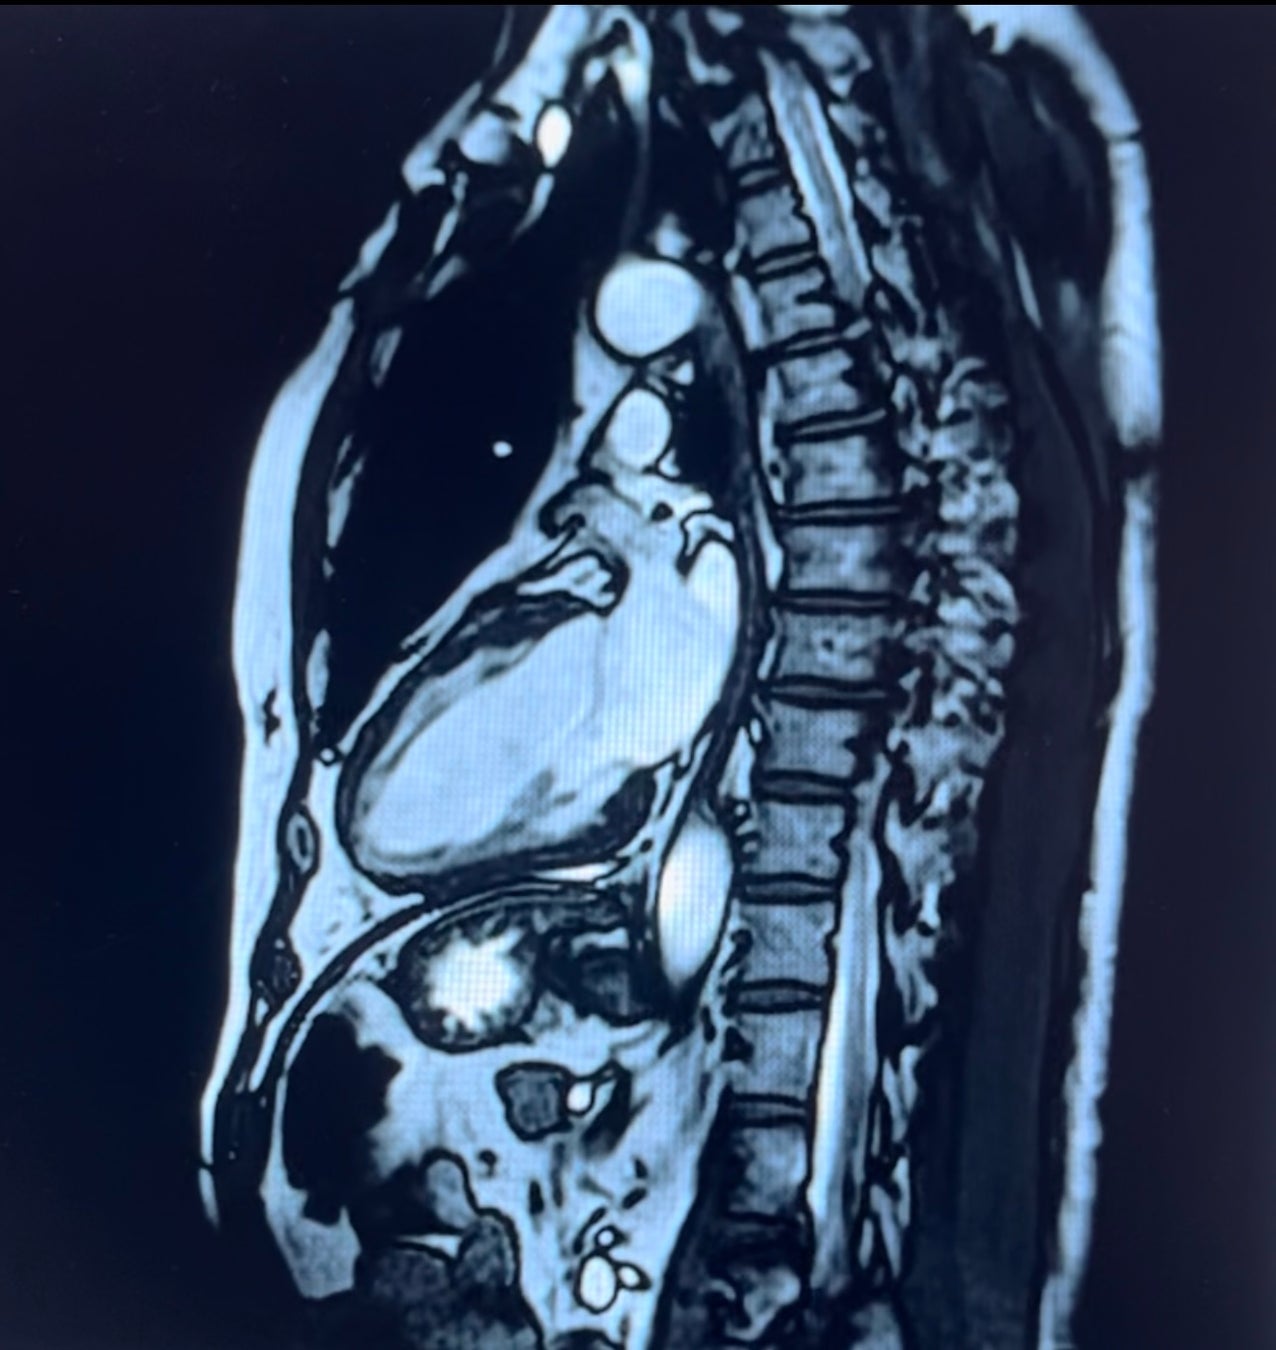

・心臓MRI

放射線を被爆することなく、心臓機能解析が複数断面で定量的に行えるようになり、三次元の動画と

して描出することが可能です。